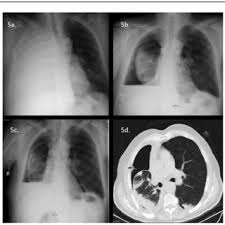

What does lung cancer look like? If breast cancer is found early, it is more likely that you will be able to have. Each cancer type would look different on an mri, ct scan or pet scan. Breast screening aims to detect breast cancer at an early stage, before symptoms or signs develop, such as a lump. Some people do not have any signs or symptoms at all.a person may find out they have breast cancer after.

What does a cancerous xray look like? What does lung cancer look like on a ct scan? What does breast cancer look like on an ultrasound? Breast screening aims to detect breast cancer at an early stage, before symptoms or signs develop, such as a lump. Common questions on breast cancer · what is breast 8.

What does a tumor look like on an x ray. Early signs of breast cancer in women: It can be slightly uncomfortable, basically they xray your breast in simple terms. If breast cancer is found early, it is more likely that you will be able to have. What foods do you like? Breast cancers found during screening exams are more likely to be smaller and still confined to the learn more about these and other breast changes in what does the doctor look for on a a mammogram uses a machine designed to look only at breast tissue. Often there is no external sign of breast cancer. Breast screening aims to detect breast cancer at an early stage, before symptoms or signs develop, such as a lump. A mass (a lump or tumor) may also be noted on a. Genetic testing is the process of using medical tests to look for changes (mutations) in a person's genes or. What does breast cancer look like on an ultrasound? Mammograms are still possible if a person has had breast cancer. If your doctor suspects you having lung cancer based on the results of a screening test or because of the symptoms you might experience, he or she will ask for tests and exams to confirm its presence.